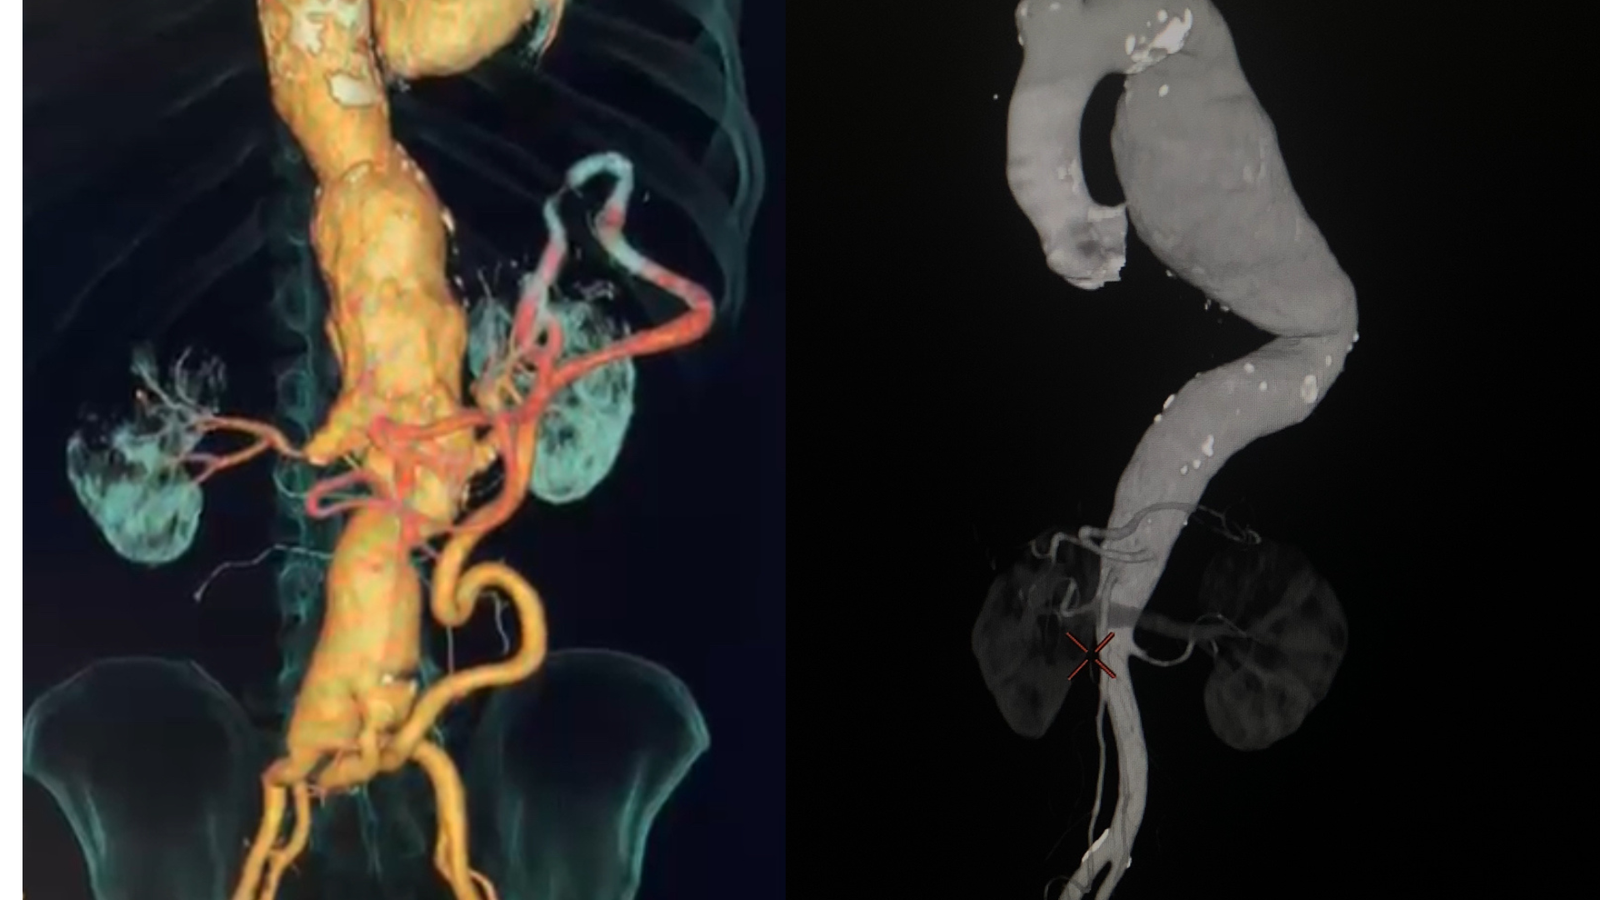

Realce Arterial Avanzado Tomografía computarizada aplicada

Programa de formación especializado en realce arterial en tomografía computarizada, enfocado en la integración adecuada de los parámetros técnicos, la fisiología del paciente y la correcta administración del medio de contraste. El curso incluye el manejo del inyector automático y las principales técnicas de sincronización del escaneo, con un enfoque práctico y clínico orientado a optimizar la calidad diagnóstica de los estudios arteriales.